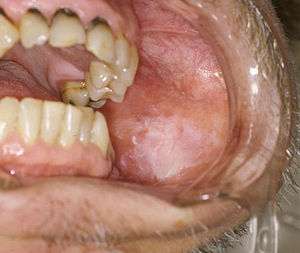

| Oral leukoplakia on the buccal mucosa. | |